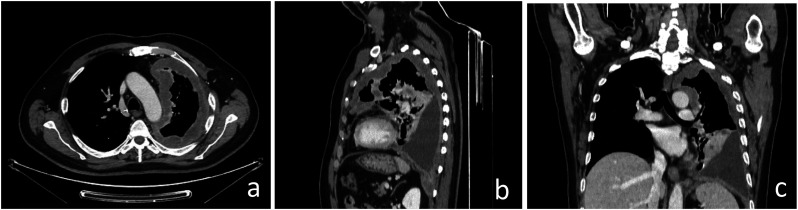

Background: Malignant pleural mesothelioma is the most common primary tumor of the pleura. The unique growth pattern of malignant pleural mesothelioma makes it difficult to apply the Response Evaluation Criteria for Solid Tumors (RECIST). Hence the need to use modified RECIST (mRECIST) criteria, as they better fit the unique growth pattern of malignant pleural mesothelioma. The thickness of the tumor perpendicular to the chest wall or mediastinum is measured at 2 points at 3 separate levels at least 1 cm apart on chest CT scans, and summed to obtain a one-dimensional pleural measurement. The same criterion has also been used to assess response to treatment. RECIST 1.1 represents a further update, taking into account new concepts such as revised minimum dimensions for lymph nodes and an approach to lesions that become non-measurable. Based on experience and published literature, the hypothesis of merging the 2 above-mentioned criteria in mRECIST 1.1 for mesothelioma and the use of iRECIST for the application to immune-based therapies (iRECIST) was considered. Purpose: Support the importance of studying pleural mesothelioma in a reliable and reproducible way, through a scrupulous methodology, applying the mRECIST1.1 and iRECIST criteria. Conclusions: Adoption of a standardized study metodology can make the study of PM reproducible and correct.

Abstract Image